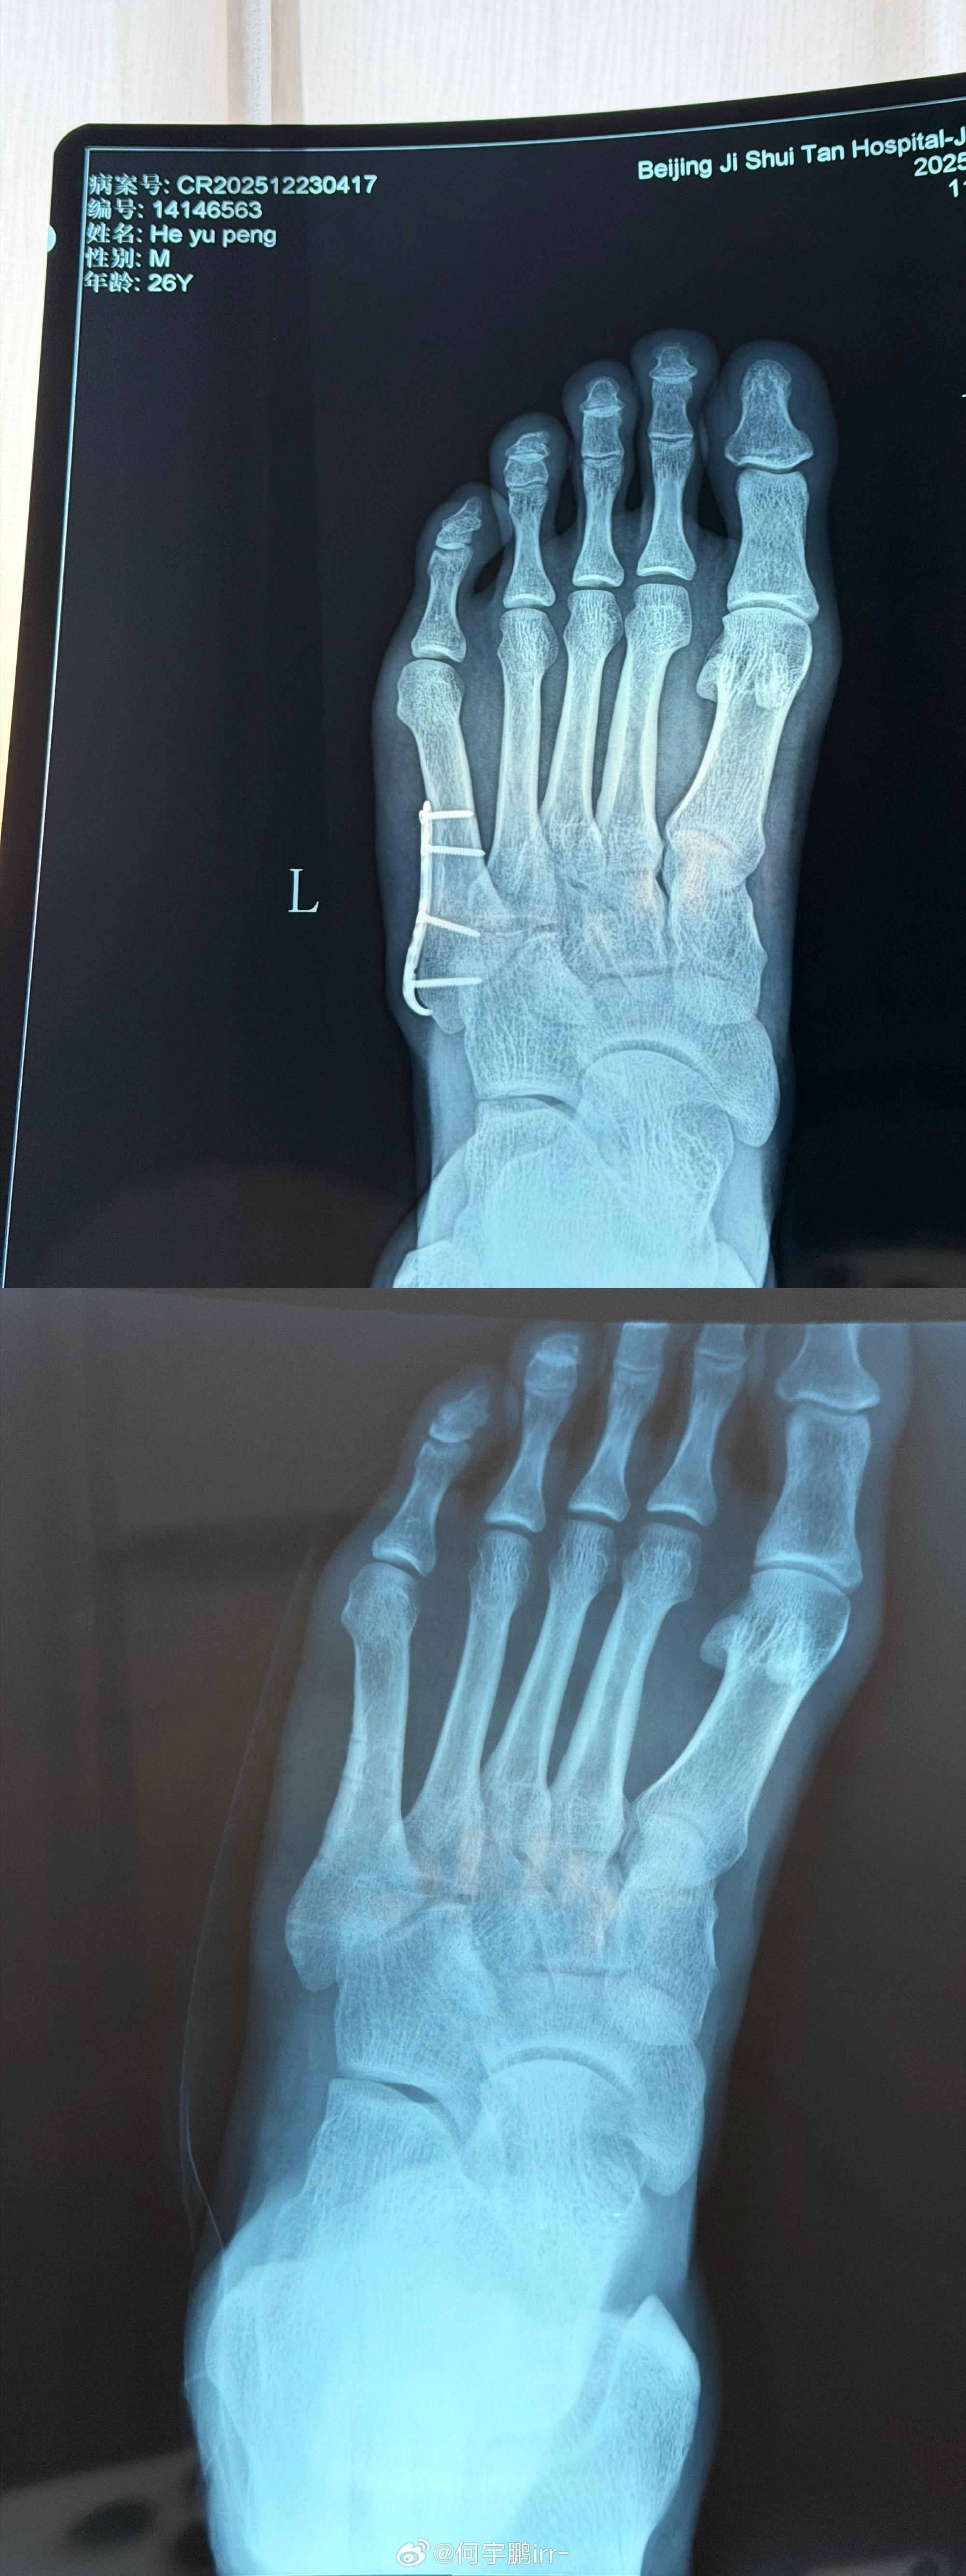

北京時間12月25日,北京國安球員何宇鵬在社交媒體上分享了自己摘除左腳鋼板的照片。

何宇鵬寫道:“終於要和身體裏這個‘鐵哥們’說再見了

雖說爲了你足球鞋都大了半碼哈哈哈!但也非常感謝8個月的保駕護航,現在,是時候說再見了! 從一開始不敢置信可以帶着鋼板踢球,到二次手術圓滿結束,都不得不提我的大功臣,感謝積水潭孫旭主任用超高的醫術精密地修補了我的身體! 也感謝葆石頭康復與 的鼎力支持!願每一次傷愈都能變得更堅韌!”